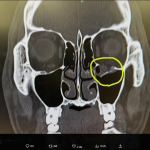

左眼窩底骨折の再手術を行ったYA-MAN